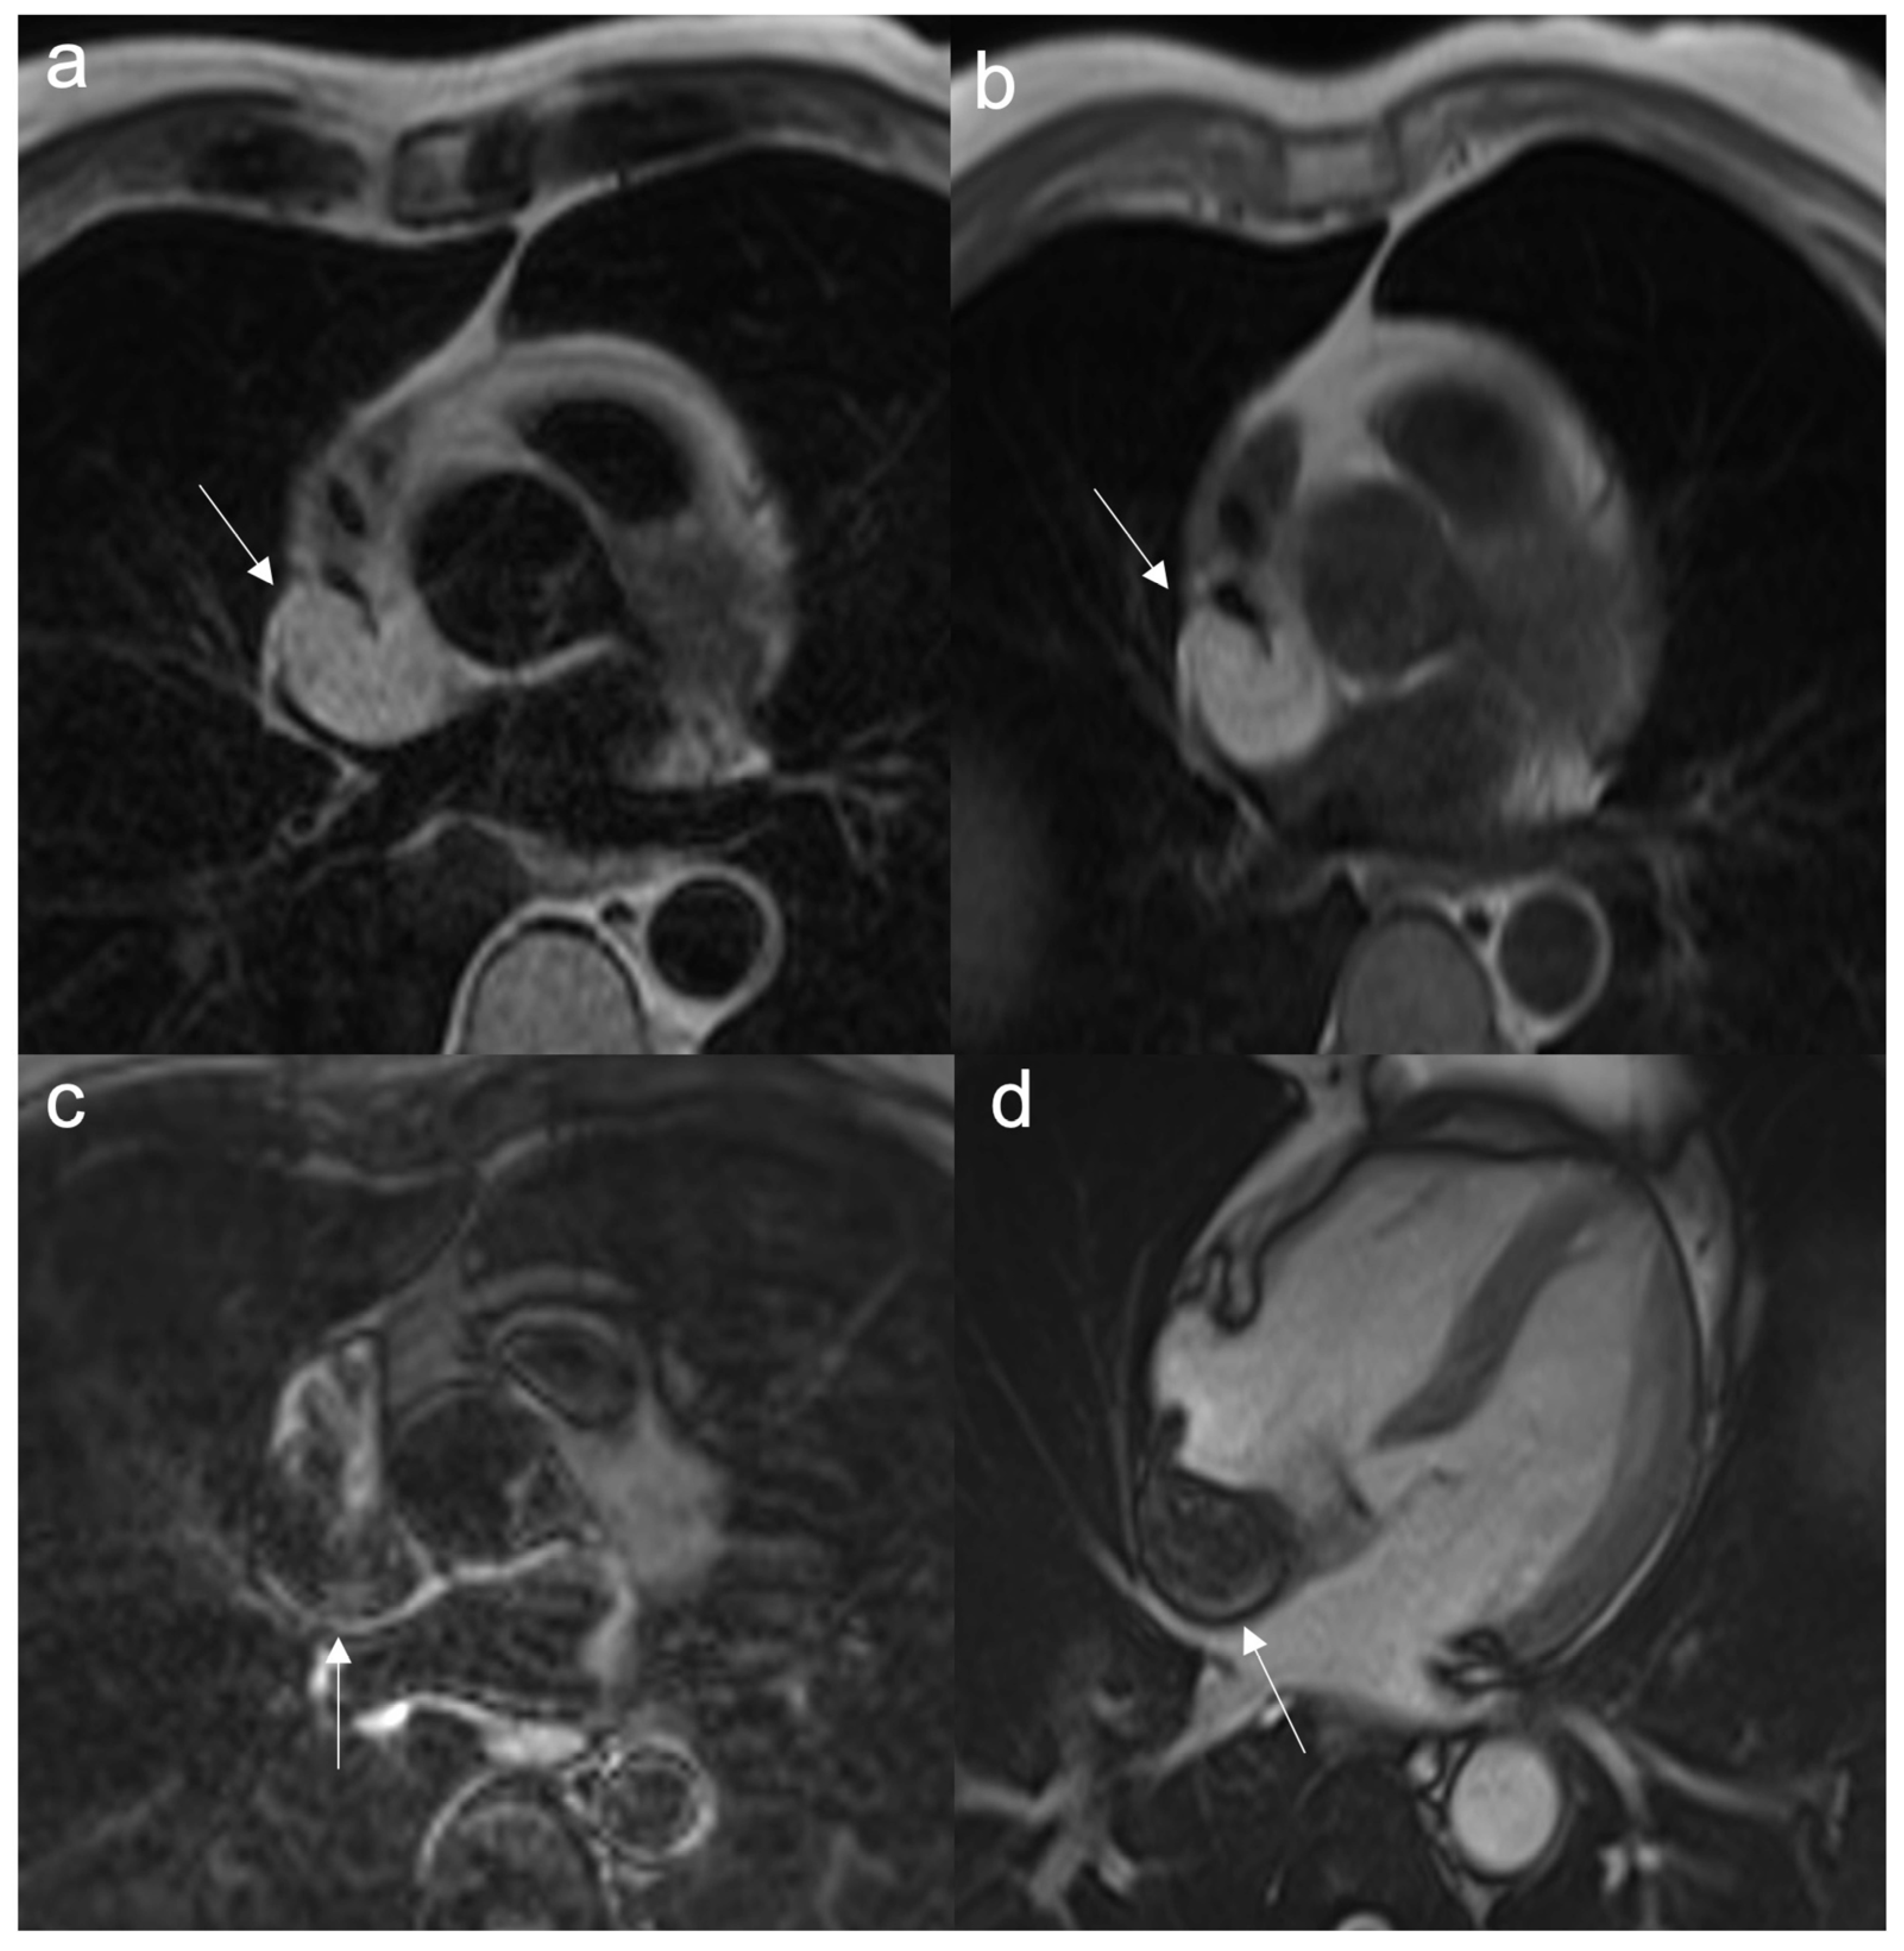

Figure 1.

A 46-year-old woman with retrosternal pain during exertion and non -ST elevation myocardial infarction underwent coronarography. The interventional procedure showed stenosis of the common trunk treated with bifurcation stent implantation. Later, due to the unexplained pericardial effusion, the patient underwent coronary computed tomography angiography (CCTA) which revealed a voluminous pseudoaneurysm (arrow) of the left coronary sinus (a,b). Cardiac surgery was performed to exclude pseudoaneurysm and to perform a by-pass (c). After the cardiac surgery, the patient performed a CCTA that showed the exclusion of the pesudoaneurysm (d). Four months later, when the patient was back for a follow-up, CT angiography showed a mass with peripheral enhancement, central hypodensity due to necrosis, and central neoangiogenesis (e). Finally, the patient underwent CMR that confirmed the presence of inhomogeneous mass invading the surrounding structures (f) and neoplasia was suspected. Lastly, the ultrasound-guided transesophageal biopsy has shown the presence of fused and pleomorphic malignant cells with leiomuscular immunophenotype (actin 1A4 +) and the diagnosis of leiomyosarcoma was made.